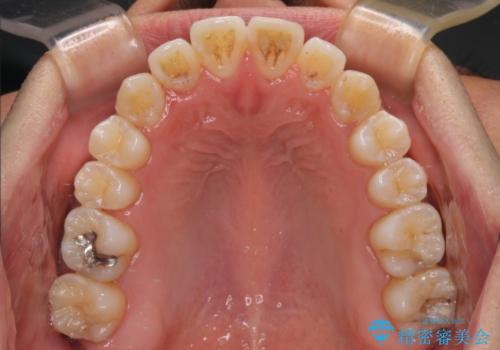

左右の八重歯が気になる ワイヤー装置での咬み合わせ改善

舌の突出癖がなかなか改善されず、上下前歯部の接触が得られるまでに予定の倍ほどの期間がかかりました。

- 4年1ヶ月